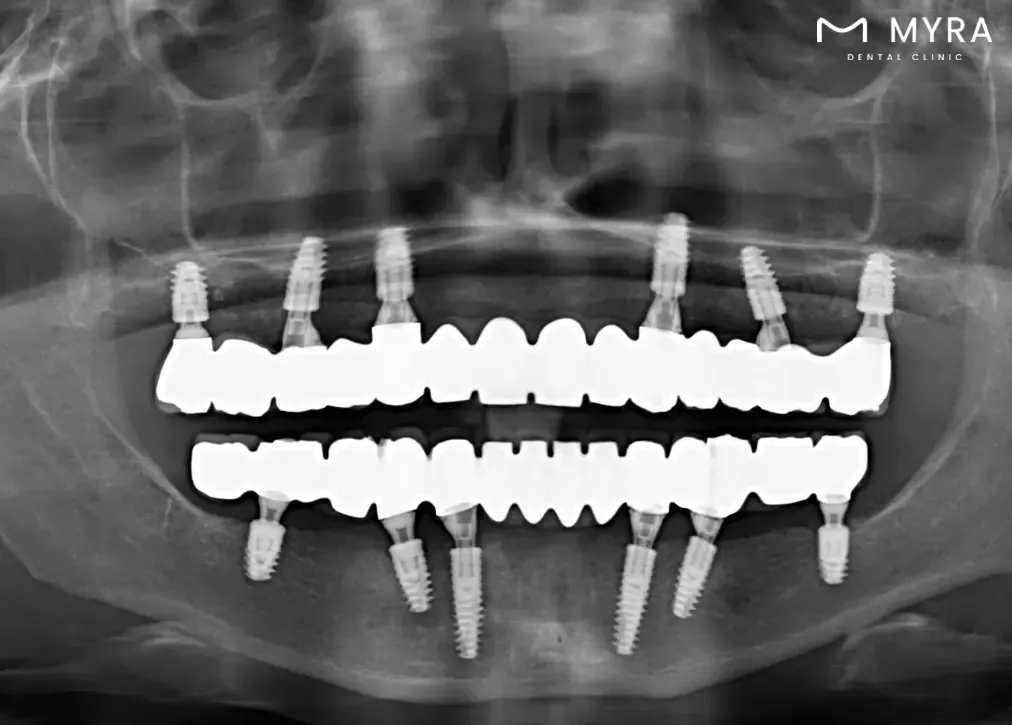

Implant Surgery Planning: Sirona 3D Dental Tomography is utilised to assess the bone structures of the jaw, allowing for precise planning of implant surgeries. The detailed images aid in determining the optimal placement of dental implants.

Detailed Imaging for Treatment Stages: The technology is frequently used in various treatment stages, including planning for implant surgery by advanced procedures, root canal treatment, and orthodontic interventions. The detailed imaging allows for precise assessments, contributing to successful outcomes in these procedures.

Efficient Planning for Implant Surgery: The technology is particularly useful in planning and guiding implant surgeries. It allows for a thorough evaluation of the jawbone structure, facilitating precise implant placement and increasing the likelihood of successful outcomes.

Sirona 3D Dental Tomography allows dentists to gain a more in-depth understanding of dental and jaw-related issues. The three-dimensional images enable precise and accurate diagnoses of conditions such as tooth decay, buried or impacted teeth, fractures resulting from trauma, bone defects, and the periodic assessment of implants.

The procedure aids in treatment planning by offering a higher level of detail and accuracy. Dentists configure root canals, measure root canal dimensions, and conduct detailed assessments of bone density, sinuses, and joints. The technology helps in the planning of dental implant procedures, offering a three-dimensional evaluation of the jawbone structure.

Imaging before Implant treatment is very important. Because the 3D tomography X ray shows the condition of the jawbone very clearly, they contribute to proper planning before surgery. Bone density is a measure of bone density. Thus, it is determined which surgical techniques will be used and exactly what can be done before the procedure begins. After surgery, CT scans can be taken to control implant placement and bone support.